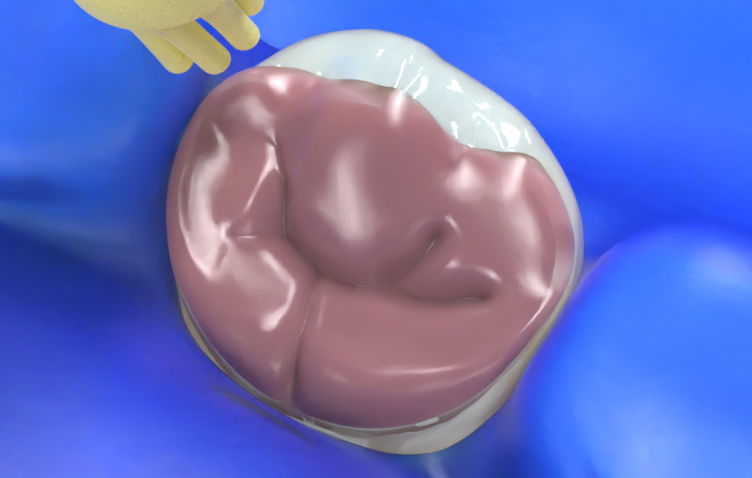

Provisorische Restaurationen

J-Temp eignet sich für die Herstellung provisorischer Restaurationen in der Endodontie, für Inlays und Onlays sowie zum Höckeraufbau.